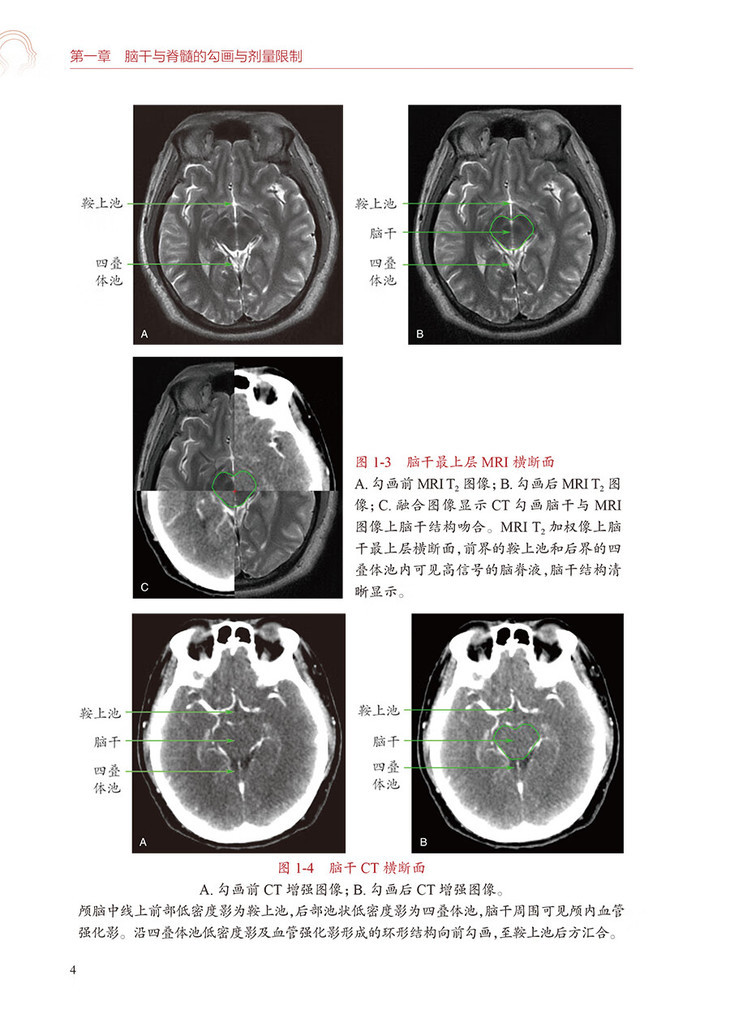

第二节勾画图谱/2